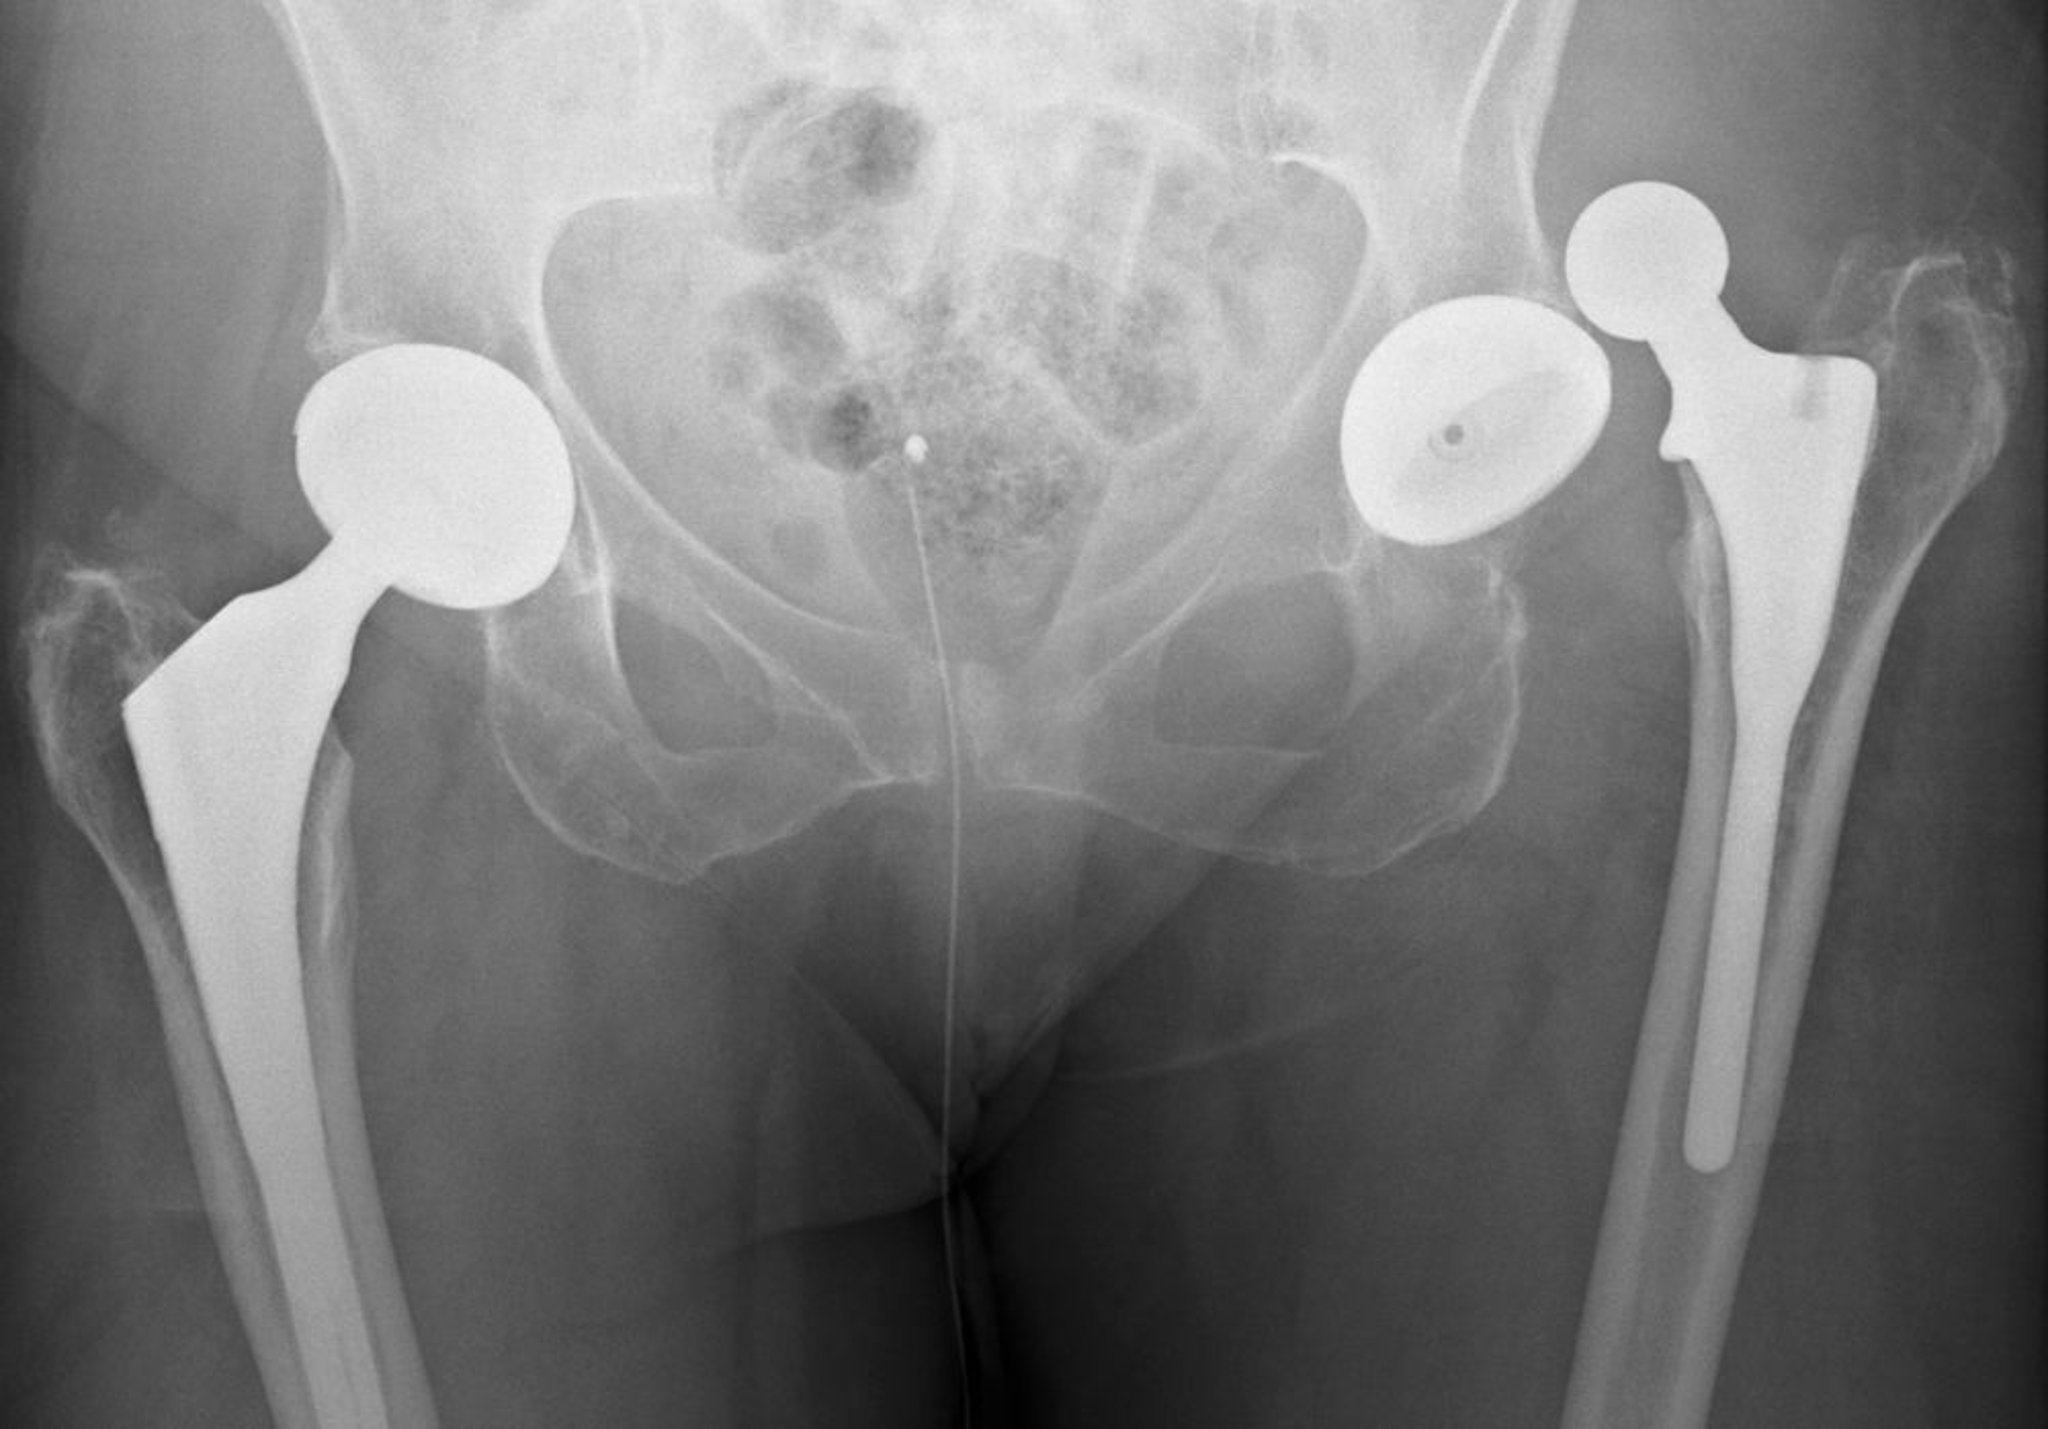

Prótesis de cadera luxada

Esta luxación es posterior.